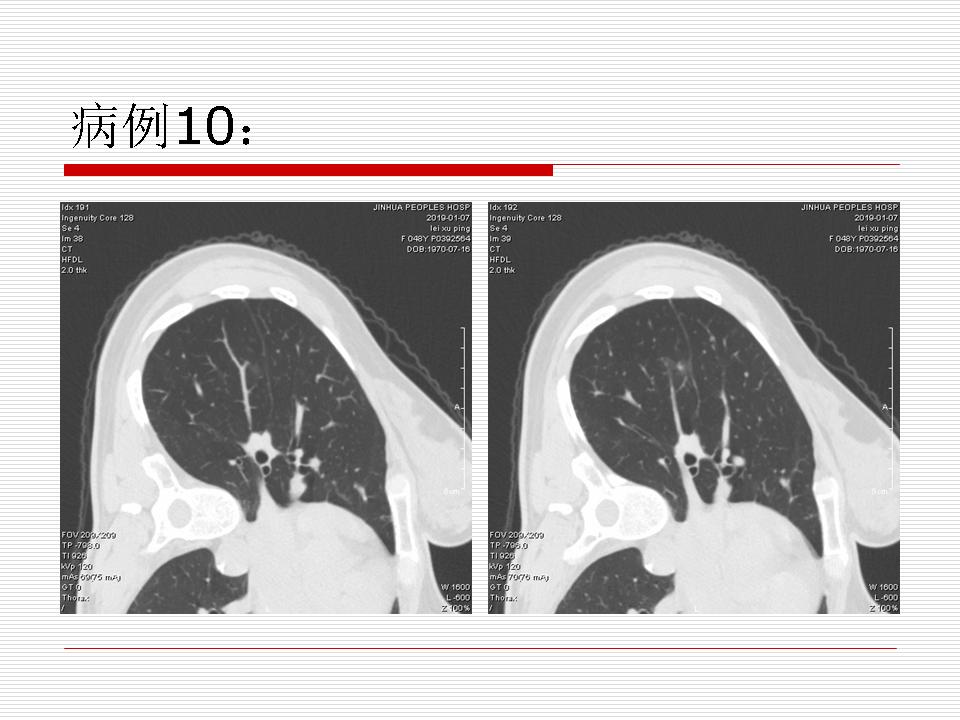

肺部阴影永恒且最重需要鉴别的是:到底是炎症还是肿瘤?但临床的病例中的影像表现难以界定或有些肿瘤特征,同时又有些炎症特点是非常常见的情况。作为临床医生我们怎么去总结分析,并找到之所以是炎症或之所以是肿瘤的细微差别或特点非常重要,也非常有用。2019.12.7浙江省2019年胸心外科学学术年会在宁波召开时,我的临床病例分析与经验总结<那些像肺癌的炎症与像炎症的肺癌>获得在大会交流的机会,以下为该PPT的内容,与你分享,希望对同道有益,有借鉴与启迪。若有探讨与进一不完善的建议,欢迎文末留言讨论: